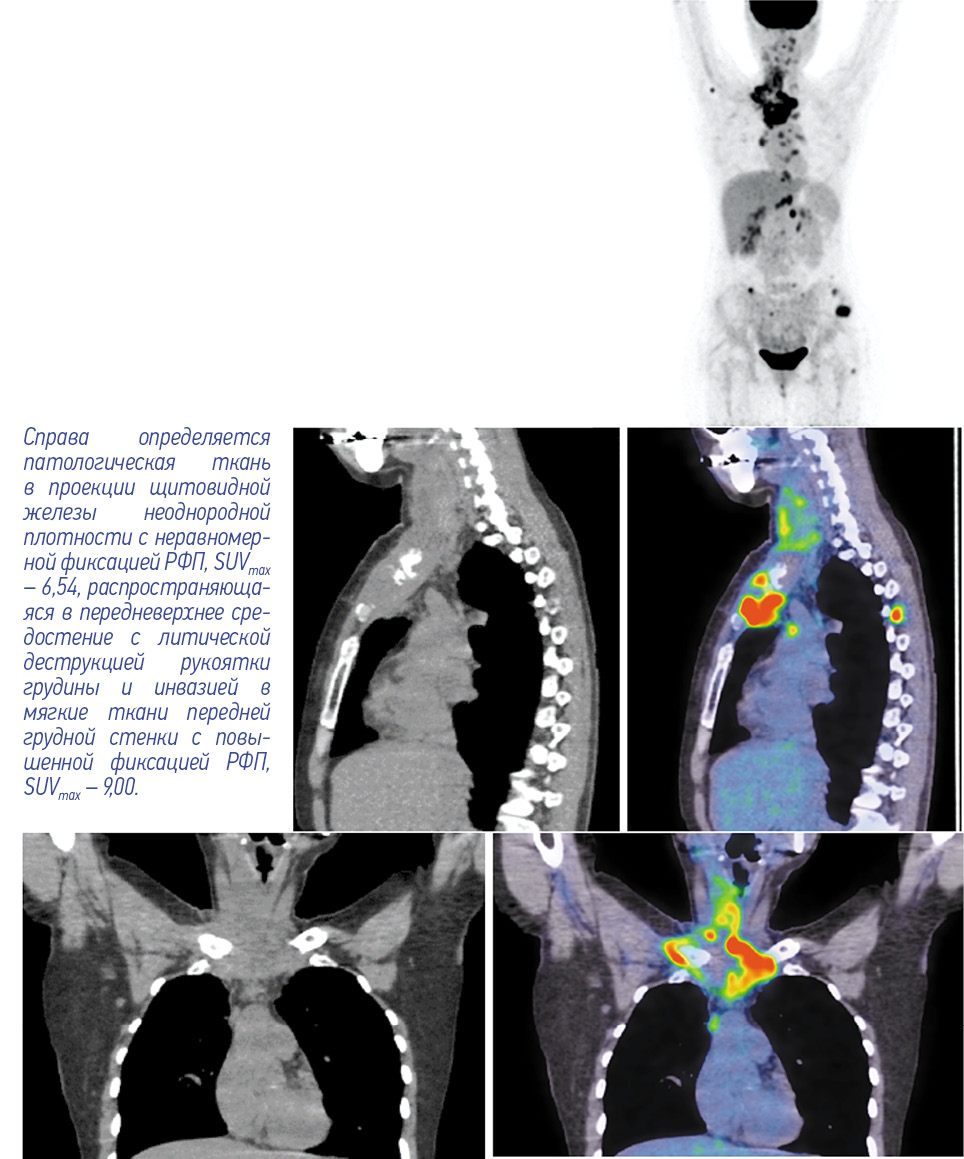

С целью уточнения распространенности опухолевого процесса выполнена комбинированная позитронно- эмиссионная и рентгеновская компьютерная томография (ПЭТ/КТ) с 18F-фтордезоксиглюкозой (ФДГ). При этом выявлены единичные шейные с фиксацией радиофармпрепарата (РФП), SUVmax – 2,90 и множественные надключичные лимфоузлы размером 16×29 мм, SUVmax – 7,90. Кроме того, в проекции щитовидной железы справа определяется патологическая ткань неоднородной плотности размером 28×38 мм, распространяющаяся в передневерхнее средостение с литической деструкцией рукоятки грудины и инвазией в мягкие ткани передней грудной стенки общим размером 91×63 мм, с повышенной фиксацией РФП, SUVmax – 9,00 (рис. 1).

Рис. 1. Пациентка Б., 41 год. ПЭТ/КТ с 18F-ФДГ до начала лечения. На MIP ПЭТ, сагиттальных и корональных КТ- и ПЭТ/КТ- проекциях определяются единичные шейные лимфоузлы IIА/В группы справа, с фиксацией РФП SUVmax – 2,90, а также многочисленные надключичные лимфоузлы справа метаболическим размером 16×29 мм SUVmax – 7,90. / Fig. 1. Female patient B., 41 years old. PET/CT with 18F-FDG before the treatment. MIP PET, sagittal and coronal CT, and PET/CT projections show solitary cervical lymph nodes of group IIA/B on the right, with a radiopharmaceutical uptake with SUVmax of 2.90, and multiple supraclavicular lymph nodes on the right with metabolic size of 16×29 mm, SUVmax – 7.90.

Согласно результатам ПЭТ/КТ, лимфоузлы шеи не увеличены, без повышенной метаболической активности. На уровне щитовидной железы патологически измененной ткани не определяется. Тем не менее в передневерхнем средостении имеется мягкотканый компонент с литической деструкцией рукоятки грудины и инвазией в мягкие ткани передней грудной стенки размером 40×32 мм по сравнению с 23×48 мм в предыдущем исследовании, с повышенной фиксацией РФП, SUVmax – 3,3 (рис. 3, 4). Кроме того, отмечается снижение фиксации РФП во вторичных очагах на фоне литической перестройки костной ткани в грудинных концах ключиц, грудине, крыле левой и правой подвздошной кости, грудных позвонках, головке правой плечевой и левой бедренной кости.

Рис. 3. Пациентка Б., 41 год. ПЭТ/КТ с 18F-ФДГ по окончании 6 циклов полихимиотерапии. На MIP ПЭТ, сагиттальных и корональных КТ- и ПЭТ/КТ-проекциях лимфатические узлы шеи не увеличены, без повышенной метаболической активности. Патологической ткани на уровне щитовидной железы не определяется. / Fig. 3. Female patient B., 41 years old. PET/CT with 18F-FDG at the end of 6 cycles of polychemotherapy. The neck lymph nodes were not enlarged on MIP PET, sagittal and coronal CT, and PET/CT views; no increased metabolic activity was observed. Abnormal tissue at the thyroid gland level was not found.